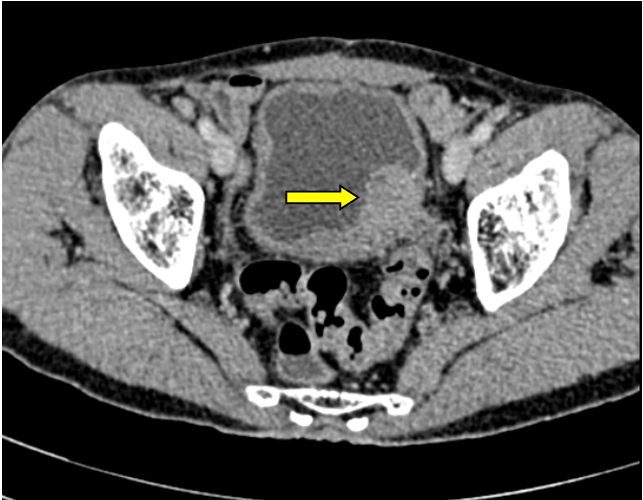

Bệnh nhân T. có tiền sử mổ sỏi bàng quang cách đây 6 năm, mổ nội soi cắt u xơ tiền liệt tuyến cách đây 1 năm. Lần này nhập viện với lý do đái máu tươi toàn bãi, thỉnh thoảng có máu cục, kèm theo triệu chứng tiểu khó, tia tiểu yếu. Qua thăm khám lâm sàng và hình ảnh chụp CT. Scanner cũng như hình ảnh soi bàng quang cho thấy người bệnh có một khối u kích thước 3x4 cm ngay lỗ niệu quản trái, đụng vào dễ chảy máu. Thực hiện cắt mẫu làm giải phẫu bệnh cho kết quả carcinoma niệu mạc, biệt hóa kém, đã xâm lấn lớp cơ bàng quang. Sau khi tiến hành hội chẩn, bệnh nhân được chỉ định phẫu thuật cắt bàng quang toàn bộ.

Hình ảnh u bàng quang của người bệnh trên phim CT.Scanner